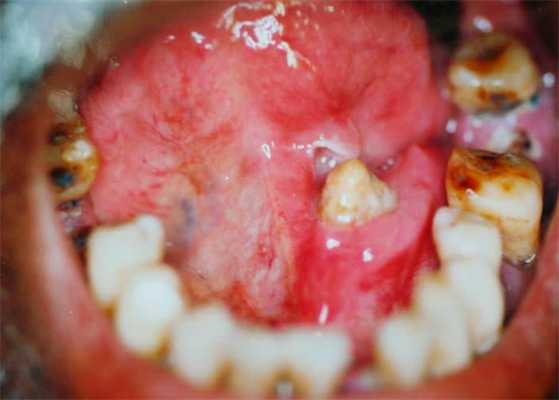

Рак (аденокарценома) слюнной железы очень опасен для здоровья, так как склонен к быстрому росту, проникновению в близлежащие органы и отделению метастаз.

Злокачественные опухоли (злокачественная плеоморфная аденома и различные карциномы);

Если есть ненормальная масса, она может не измениться по размеру или даже исчезнуть. В отличие от закупорки, опухоль из-за массы не изменяется в зависимости от потребления пищи. Большинство масс, выращенных в подчелюстной железе, вызваны доброкачественными опухолями, такими как афтома или опухоль Вартина. Эти опухоли обычно безболезненны и легко перемещаются при пальпации. Даже если они доброкачественны, опухоли должны быть удалены, потому что они не будут лечить себя сами и будут продолжать расти со временем, вызывая искажение лица. Обычно после десятилетий эти доброкачественные опухоли также могут развиваться в рак (карцинома в плевральной аденоме).

К сожалению, некоторые массы могут быть раковыми и включать мукоэпидермоидную карциному, базально-клеточную карциному и метастазы от рака кожи (наиболее распространена плоскоклеточная карцинома). Если есть боль, онемение над подбородком или зубами, языком или ртом, или паралич лица, вероятность того, что масса является злокачественной, увеличивается.